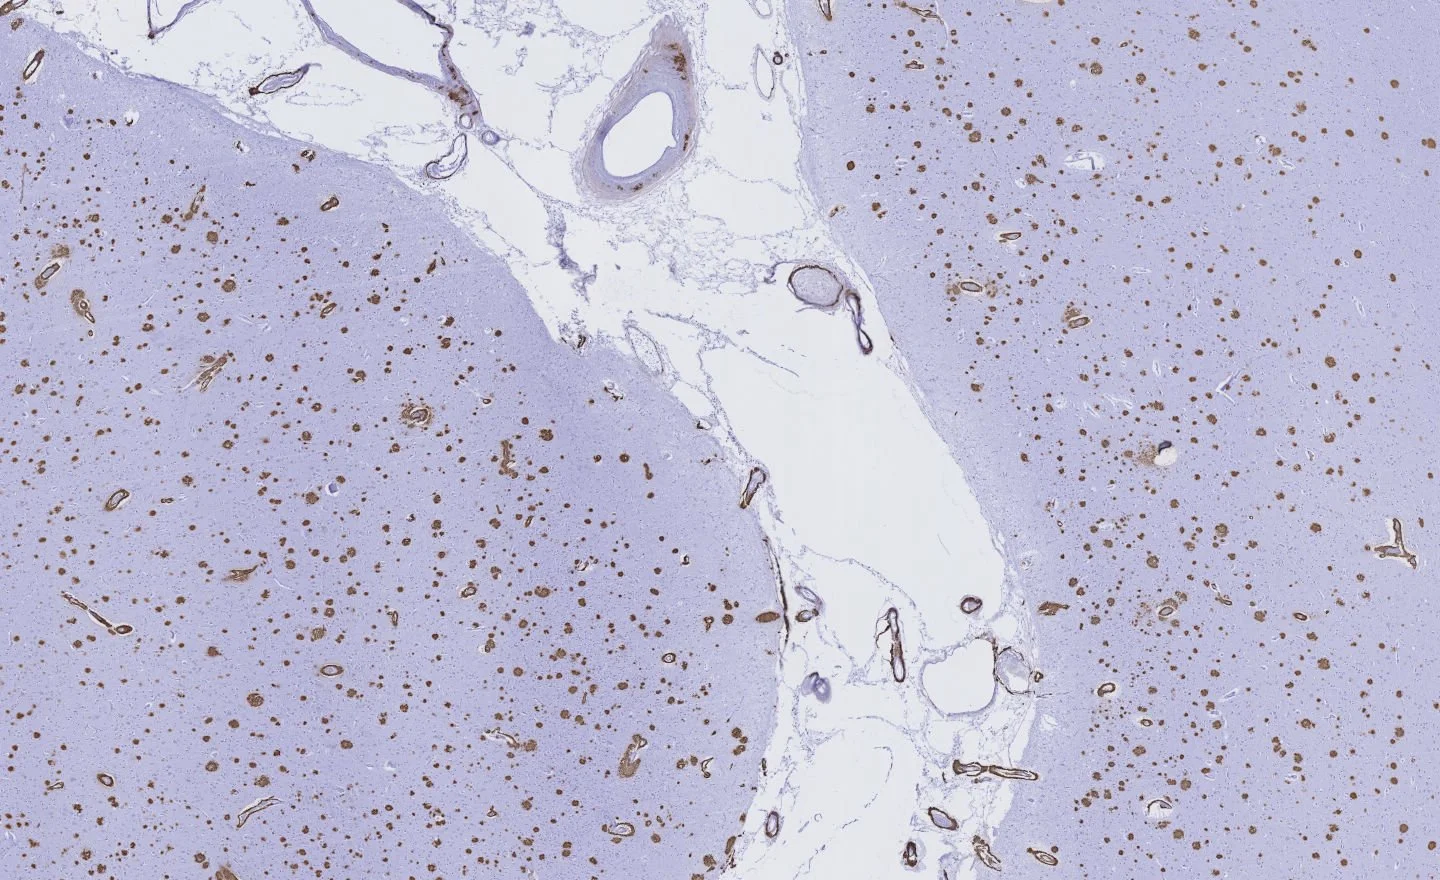

Ongoing studies aim to elucidate the mechanisms by which microvascular injury is linked to the accumulation of proteinopathies like amyloid-β and tau, with an emphasis on brain clearance dysfunction and blood brain barrier leakage. Furthermore, we investigate the role of subcortical vascular pathology and enlarged perivascular spaces in driving white matter injury. To address these questions, we employ a multimodal approach, combining in vivo and ultra-high-resolution ex vivo neuroimaging, AI-based quantitative pathology, three-dimensional histology, and super-resolution microscopy.